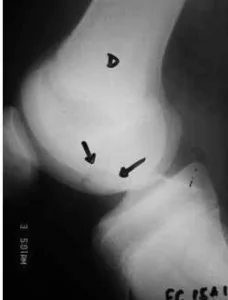

O local mais comumente afetado é a face posterolateral do côndilo femoral medial (75%) (figura 1), zona de carga (onde há transmissão de peso) dos côndilos femoral medial e lateral (20%) e superfície patelar (5%).

Exame radiográfico da localização clássica da OCD na face posterolateral do côndilo femoral medial.

(A) Incidência anteroposterior.

(B) Incidência de perfil.

(C) Incidência posteroanterior (túnel).